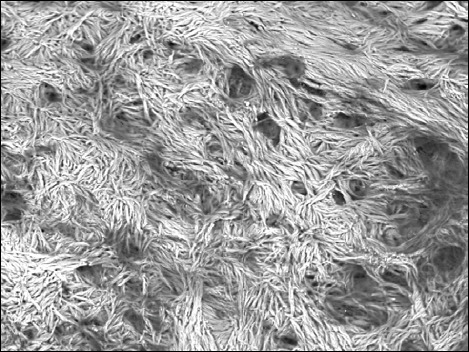

Results: The concentration of Ca2+ in the study group was significantly lower in the area of the anterior crus of the stapes than in the posterior crus. A reduction in the Ca2+/P3+ ratio in the anterior crus was associated with deteriorated bone conduction and tinnitus. Degradation of the stapes microstructure in the area of otosclerotic lesions was observed with scanning electron microscopy.

Conclusions: Bone remodelling is most significant at the closest location to typical otosclerotic lesions with hydroxyapatite porosity and scale-like bone formation according to scanning electron microscopy. There is a relationship between the disturbance of calcium metabolism and the development of clinical symptoms of cochlear otosclerosis.